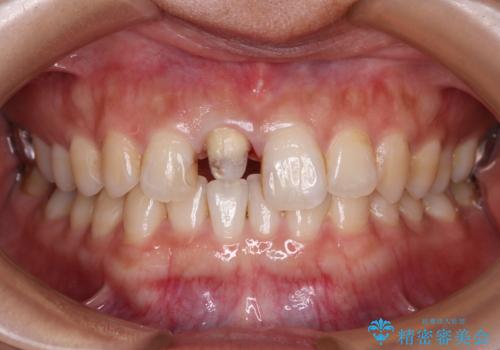

- 数年前に他院で治療した右上の前歯の色が不自然なことを主訴として来院された患者様です。

隣在歯と色、形ともに合っていません。

また、被せものと土台の境目が歯肉よりも上に見えていて、段差になっています。

そのため審美性、清掃性どちらの観点からもあまりよくない状態です。